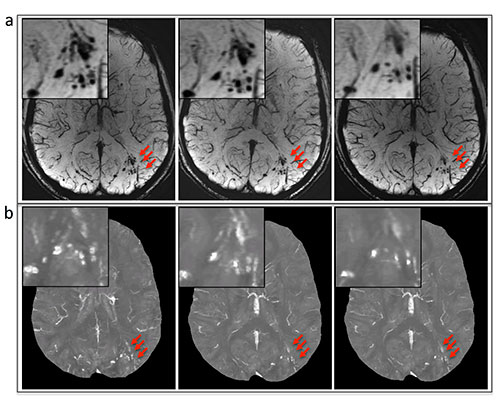

Among the 603 patients, cerebral microhemorrhages were identified in 43 patients, with six excluded for fur­ther analysis owing to artifacts. Seventy-seven percent (451 of 585) of the microhemorrhages on susceptibility-weighted images had a more conspicuous appearance than on gradient-recalled-echo images. Thirteen of the 37 patients underwent follow-up imaging examinations. In these patients, a smaller number of microhemorrhages were identified at follow-up imaging compared with base­line on quantitative susceptibility maps (mean ± standard deviation, 9.8 microhemorrhages ± 12.8 vs. 13.7 microhe­morrhages ± 16.6; P = .019). Quantitative susceptibility mapping–derived quantitative measures of microhemor­rhages also decreased over time: -0.85 mm3 per day ± 1.59 for total volume (P = .039) and -0.10 parts per bil­lion per day ± 0.14 for mean magnetic susceptibility (P = .016).

“In the current study we found that the number of micro­hemorrhages and QSM-derived mea­surements of microhemorrhages all decreased over time, suggesting that he­mosiderin products undergo continued, subtle evolution in the chronic stage of TBI. Furthermore, by correlating microhemorrhages with regional brain volumes, abnormalities such as fiber discontinuities or hyperintensities on T2-weighted fluid attenuation inversion-recovery images will facilitate the inves­tigation of this disease,” the authors write.

A, susceptibility-weighted imaging and, B, quantitative susceptibility mappingimages show the evolution of microhemorrhages (arrows) in a patient who underwent fol­low-up imaging.

Figure 2: A, susceptibility-weighted imaging and, B, quantitative susceptibility mappingimages show the evolution of microhemorrhages (arrows) in a patient who underwent fol­low-up imaging.